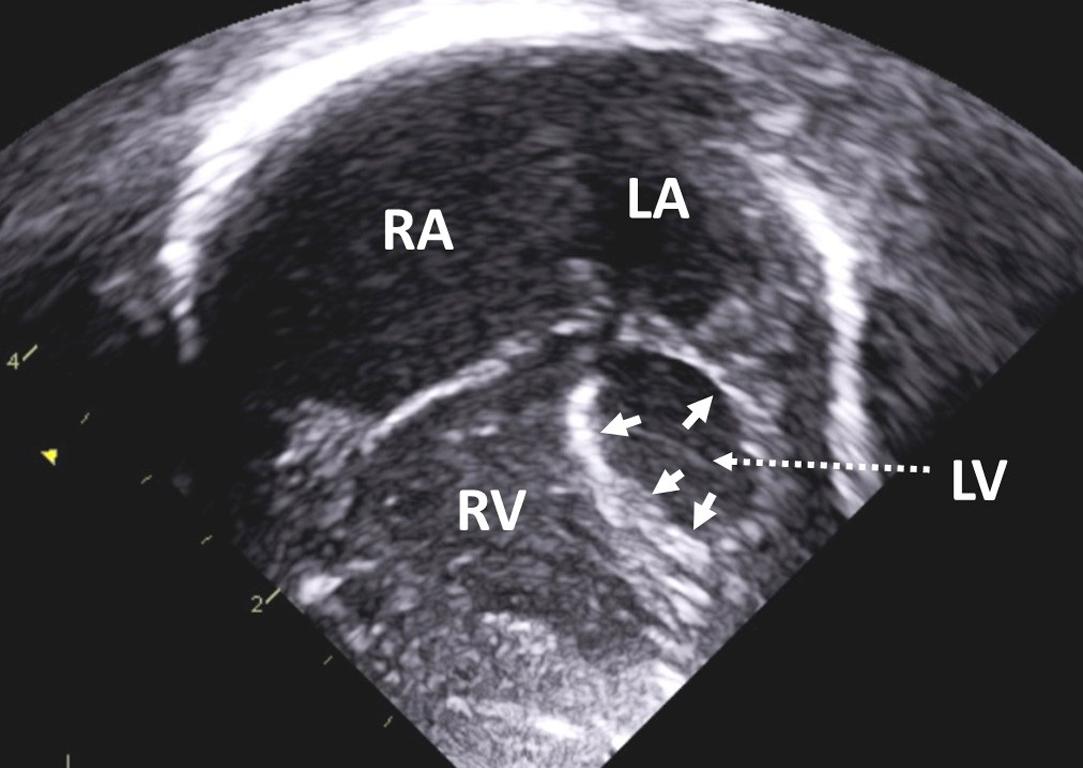

Figure 1, Apical four-chamber view in a neonate with hypoplastic left heart syndrome and severe mitral and aortic stenosis. The left ventricle is diminutive, nonapex forming, and dysfunctional. Note the presence of endocardial fibroelastosis ( arrows ). LA , left atrium; LV , left ventricle; RA , right atrium; RV , right ventricle.